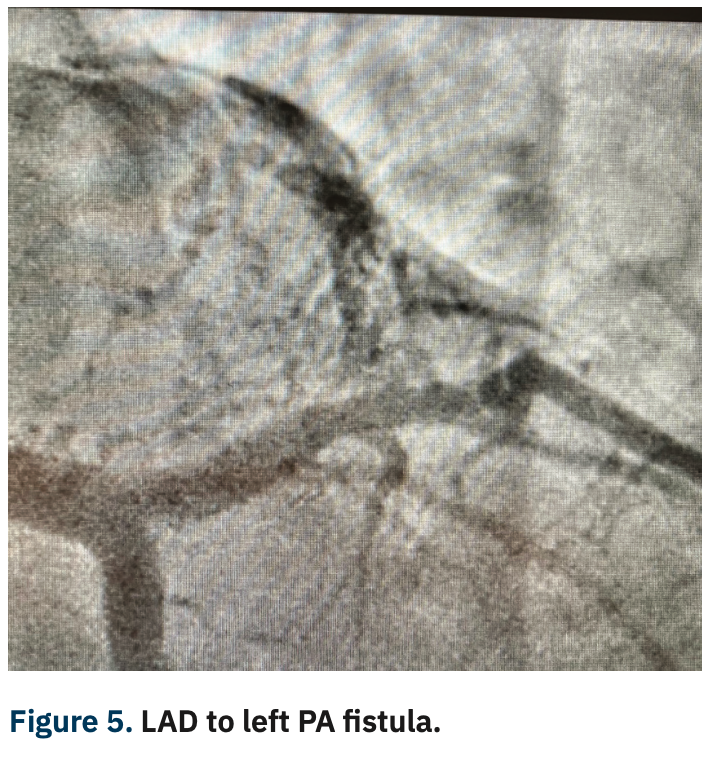

She underwent a coronary angiogram via right radial artery approach utilizing the hyper adducted right radial artery (HARRA) method3 (Figure 1), with angiography showing a normal left main and left circumflex coronary artery. There was a 50% stenosis in the mid LAD and mid right coronary arteries (Figure 2). Angiography also revealed a fistula connection between the proximal LAD and the left pulmonary artery, as well as the conus branch of the RCA and right pulmonary artery (Figures 3-5).